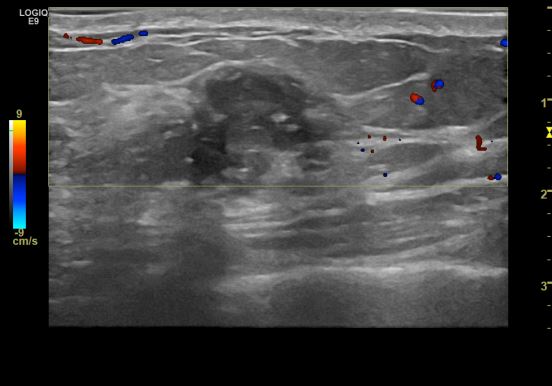

상기환자 건강검진상 이상소견으로 내원하신 50대 여성분으로  본원초음파상 우측

상내측 으심스러운 멍울 조직검사 시행하여 우측 침윤성 유관암 진단되었습니다.